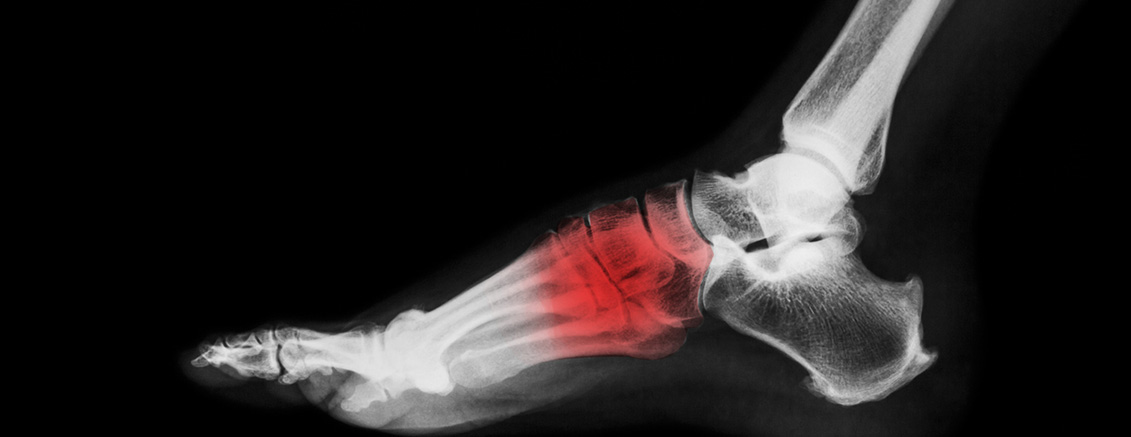

¹ß°ú ¹ß¸ñÀÇ ÅëÁõÀº Àϻ󿡼 ÈçÈ÷ Á¢ÇÏ´Â ¹®Á¦·Î Áß³â ÀÌÈÄ Àα¸ Áß ¾à 20%°¡ ¹ß°ú ¹ß¸ñÀÇ ÅëÁõÀ» È£¼ÒÇϰí, Àý¹Ý °¡·®ÀÇ È¯ÀÚ¿¡¼ º¸Çà Àå¾Ö µîÀÇ ±â´ÉÀû ¹®Á¦¸¦ °®½À´Ï´Ù. ÀÛÀº Áõ»óÀ» ´ë¼ö·ÓÁö ¾Ê°Ô ³Ñ±â´Ù°¡ ÁúȯÀÌ ½ÉÇØÁö´Â °æ¿ì¸¦ ¹æÁöÇϱâ À§ÇØ Àå±â°£ÀÇ ÅëÁõÀ̳ª ÀÌ»óÀÌ ¹ß°ßµÈ´Ù¸é Àü¹®ÀÇ¿Í »ó´ãÇÏ´Â °ÍÀÌ Áß¿äÇÕ´Ï´Ù.

¹ßÀ» Á¢Áú¸° ÈÄ ¹ß¸ñÀÇ Àü°ÅºñÀδë ȤÀº Á¾ºñÀÎ´ë µîÀÇ ¼Õ»óÀ¸·Î ¹ß¸ñ ÅëÁõ, ºÎÁ¾ÀÌ ¹ß»ýÇÏ´Â °ÍÀ» ¸»ÇÕ´Ï´Ù. Àδ밡 ¼Õ»óµÈ °æ¿ì ¿ÜÃø °üÀýÀÇ ¾ÈÁ¤¼ºÀÌ ¶³¾îÁö°Ô µÇ¸ç ÀûÀýÇÑ Ä¡·á°¡ µÇÁö ¾ÊÀ» °æ¿ì ¸¸¼ºÀûÀ¸·Î ¹ß¸ñÀ» ½±°Ô »ß°Ô µÇ¸ç ÅðÇ༺ °üÀý¿°ÀÌ ´õ »¡¸® ¹ß»ýÇÒ ¼ö ÀÖ½À´Ï´Ù.

¹ß¹Ù´Ú ±ÙÀ°À» °¨½Î°í ÀÖ´Â ¸·¿¡ »ý±ä ¿°ÁõÀ» ¸»ÇÕ´Ï´Ù. ¹ßµÚ²ÞÄ¡»ÀÀÇ Àü³»Ãø°ú ´Ù¼¸ ¹ß°¡¶ô»À¸¦ À̾î ÁÖ´Â Á·Àú±Ù¸·Àº ¹ßÀÇ ¾ÆÄ¡¸¦ À¯ÁöÇÏ°í ¹ß¹Ù´ÚÀÌ ¹Þ´Â Ãæ°ÝÀ» Èí¼öÇÏ´Â ¿ªÇÒÀ» ÇÕ´Ï´Ù. ÀÌ·± Á·Àú±Ù¸·¿¡ ¹Ýº¹ÀûÀ¸·Î ¹Ì¼¼ÇÑ ¼Õ»óÀÌ ÀϾ¸é¼ ¿°ÁõÀÌ ¹ß»ýÇÑ °ÍÀ» 'Á·Àú±Ù¸·¿°' À̶ó°í ÇÕ´Ï´Ù.